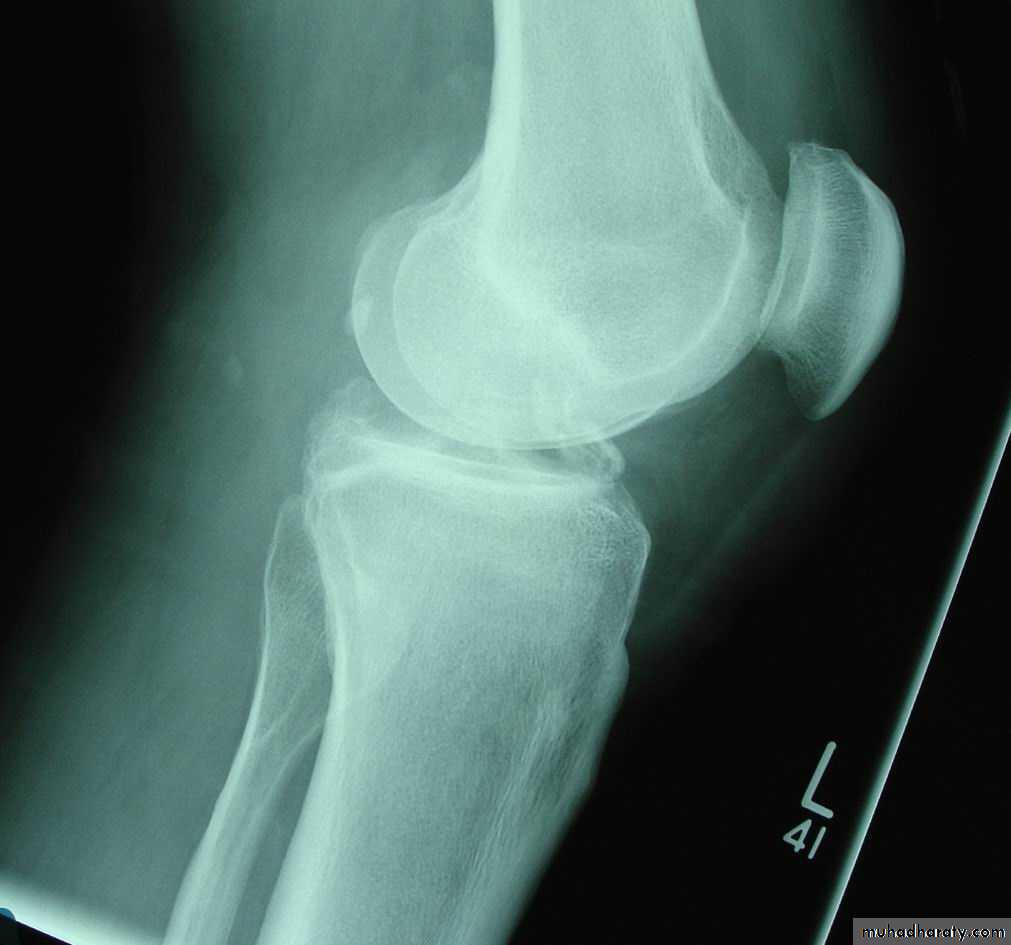

XR : normal

Pain & swellingXR : fragmentation